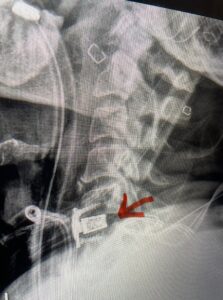

This 61-year-old female with a history of severe osteoporosis and a prior history of a laminectomy from l2-S1 with an L5-S1 instrumented fusion, presents with progressive low back pain and right lower extremity radiculopathy. MRI revealed a grade 1 L2-3 spondylolisthesis with severe stenosis mainly from severe right L2-3 facet joint hypertrophy which was compressing the right L3 descending nerve root. (Fig. 1). She had failed conservative management consisting of physical therapy and pain management with epidurals. She underwent an L1-3 revision laminectomy where we had to dissect a plane underneath the inferior aspect of the L2 lamina. We performed an instrumented fusion at L2-3 with special hydroxyapatite-coated screws to improve fixation to surrounding bone given here severe osteoporosis (Fig. 2) This worked out well and the patient had an uneventful recovery with relief of her leg pain.

Figures 1a: Sagittal and axial T2-weighted lumbar MRIs demonstrating a grade 1 L2-3 spondylolisthesis (red arrow) with severe stenosis secondary to right L2-3 facet hypertrophy (red arrow).

Fig 1b: Note the left L2-3 facet joint (blue arrow) is normal in size compared to the right (red arrow)

Fig: 2a: AP and lateral intraoperative fluoroscopic images demonstrating good placement of L2-3 pedicle screws